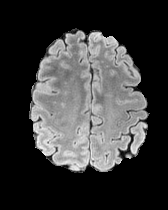

In Figures 2 and 4 we display examples of healthy images and anomaly maps obtained with the different approaches. We can observe that f-Ano GAN is not able to generate credible counterfactuals and generally produces images of poor quality and unrealistic appearance. On the other hand, the approaches based on diffusion models are able to create more high-quality results. However, the ones obtained with CG and CFG seem to present some artifacts, which may not only impact the realism of the counterfactual examples but also the precision of the anomaly maps obtained from them. In order to better quantify the capability of these methods to accurately segment pathological areas, we compute the Dice scores of the anomaly maps they generate.

We also test our approach on healthy samples. Ideally, we would like our generative process to act as the identity function when given a normal image as input. Some examples are shown in Figure 6, where we can observe that the changes introduced by our sampling technique are relatively minimal and Dif-fuse preserves the structure and general appearance of the images.